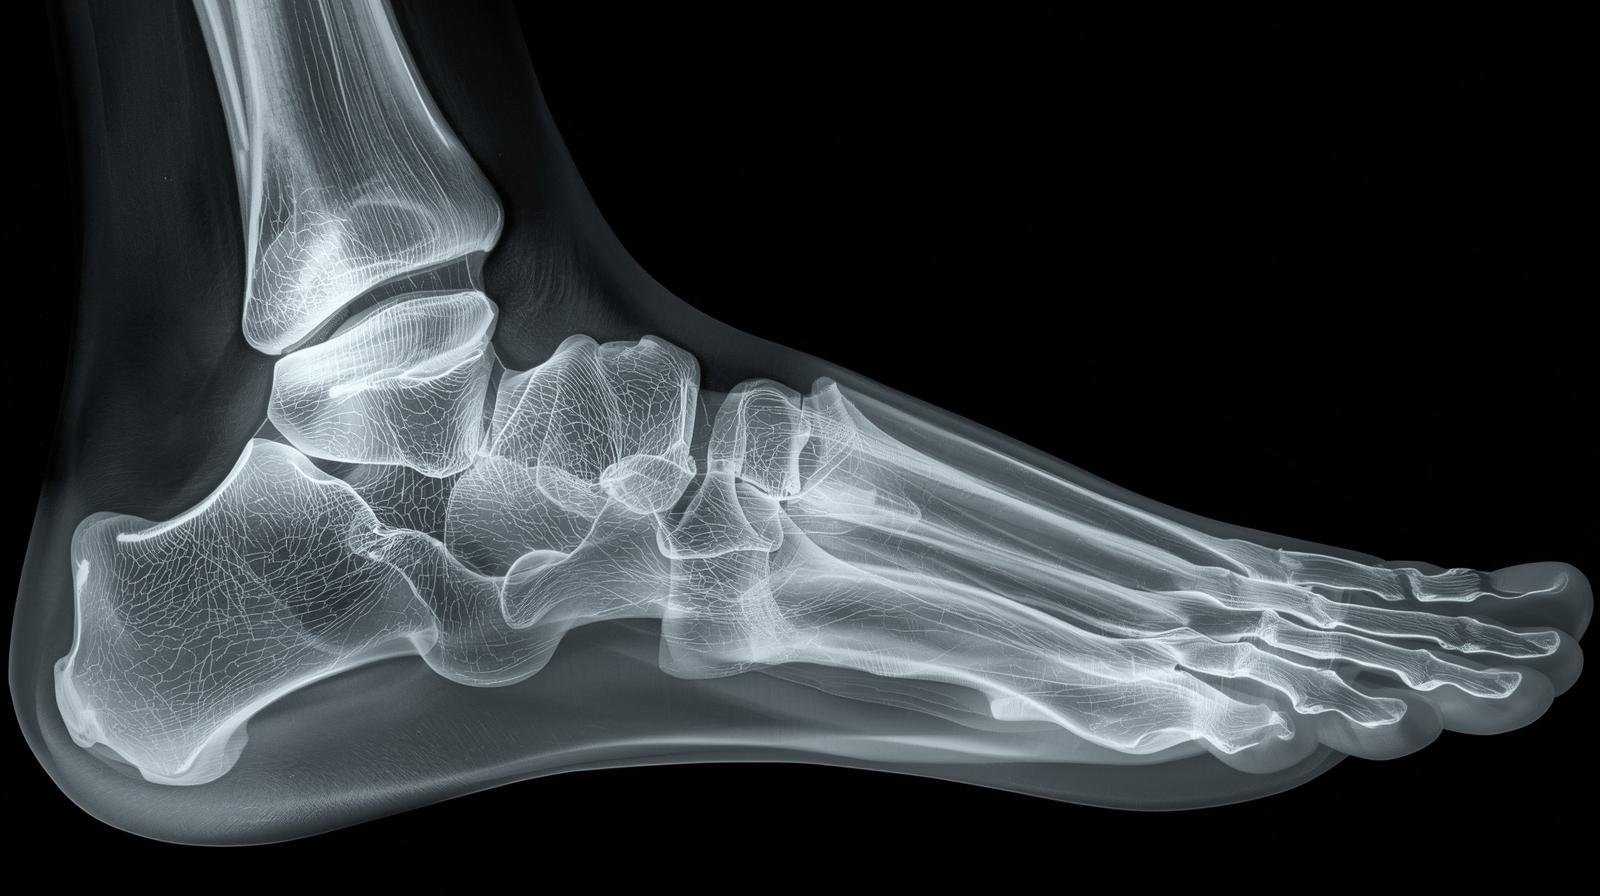

Vücudumuzdaki kemiklerin kırılması her insanın başına gelebilecek üzücü bir olaydır. Toplumda da bu konu ile ilgili yanlış bir çok bilgi dolaşmaktadır. Kemik kırıkları ile ilgili bazı gerçekler şunlardır;

Vücudumuz herhangi bir darbe aldıktan sonra ciddi bir sorun olup olmadığını anlamak için o bölgeyi rahat kımıldatabiliyor muyuz diye sorulur. Kımıldatıyorsak herhangi bir kırık yok diye düşünülür.

Oysa bazen kırık bir kemiği kımıldatmak mümkündür. Bu nedenle kemikte çatlak olup olmadığını anlamada bir kriter değildir bu.

Kırığın üç belirtisi ağrı, şişme ve şekil bozukluğudur. Ayrıca olay anında kırılma sesi duymak da mümkündür.

Ayak parmağı kırıldığında bir şey yapılmadığı için doktora görünmek gerekir mi?

Ayak parmağındaki kırık ve çatlaklarda alçıya alma söz konusu olmasa da kırığın çapını belirlemek ve uzun vadede ağrı ve deformasyona engel olmak için doktora görünmek gerekir. Kırık kötü bir açıda oluşmuşsa daha karmaşık bir tedavi, hatta ameliyat gerekebilir.

Kırık ayak parmakları çoğu zaman yanındaki parmaklara yapışık şekilde tutulur ve sert bir kalıp takılabilir. İyileşme süreci 4-6 haftadır. Ancak ayak baş parmağındaki kırıklar daha ciddidir ve bazen baldıra kadar alçıya alınıp 2-3 hafta bekletmek gerekebilir. Ama bunların kırılma ihtimali diğer parmaklardan daha düşüktür.

Kırık ayak tarağında ise, yandaki kemikler doğallığından birbirini düz tuttuğu için alçıya gerek olmaz ve ayak dinlendirildiği takdirde çoğu zaman düz bir şekilde iyileşir. Ancak baş ve küçük parmağın altındaki kemiklerin desteği olmadığından bunlarda ameliyat gerekebilir.

Alçıya almak gerekmese bile ayak parmaklarındaki kırık ve çatlakları doktora göstermek gerekir. Sağlık görevlileri parmağa destek olacak şekilde sargı takabileceği gibi, koltuk değneğine ihtiyaç olup olmadığını da belirleyebilir.